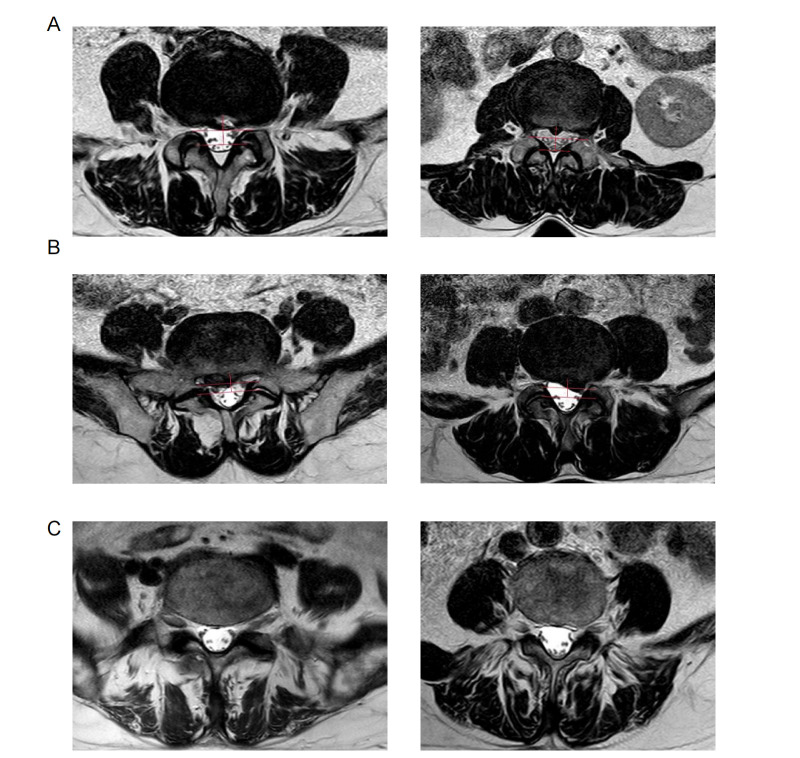

Aims: While MRI serves as a tool for assessing the severity of lumbar disc herniation (LDH), it has been observed that imaging diagnoses do not always align with clinical symptoms in nearly half of patients. The absence of dependable prognostic biomarkers impedes the early and accurate diagnosis of LDH, which is critical for the development of further treatment approaches. Thus, the aim of this study was to elucidate the molecular mechanisms that determine pain and LDH severity.

Methods: We conducted a pilot study with 55 patients, employing transcriptomic and metabolomic analyses on blood samples to identify potential biomarkers. A gene-metabolite interaction approach helped in identifying the pivotal pathway linked to disease severity. Moreover, a machine-learning model was designed to differentiate between patients based on the intensity of pain.

Results: Cholinergic-related glycerophospholipid metabolism emerged as the predominant enriched pathway in the severe symptom group via gene-metabolite interaction network analysis. Among various models, the gradient boosting machines (GBM) model stood out, achieving a commendable area under the curve (AUC) of 0.875 in distinguishing between the severe and mild symptom groups using combined RNA and metabolomics data.

Conclusion: Integrated molecular profiling of blood biomarkers has highlighted a novel determining pathway for LDH severity. This machine-learning approach can serve as a valuable predictive tool when MRI findings are inconclusive. Future research will focus on validating these biomarkers and exploring their potential for personalized medicine approaches.